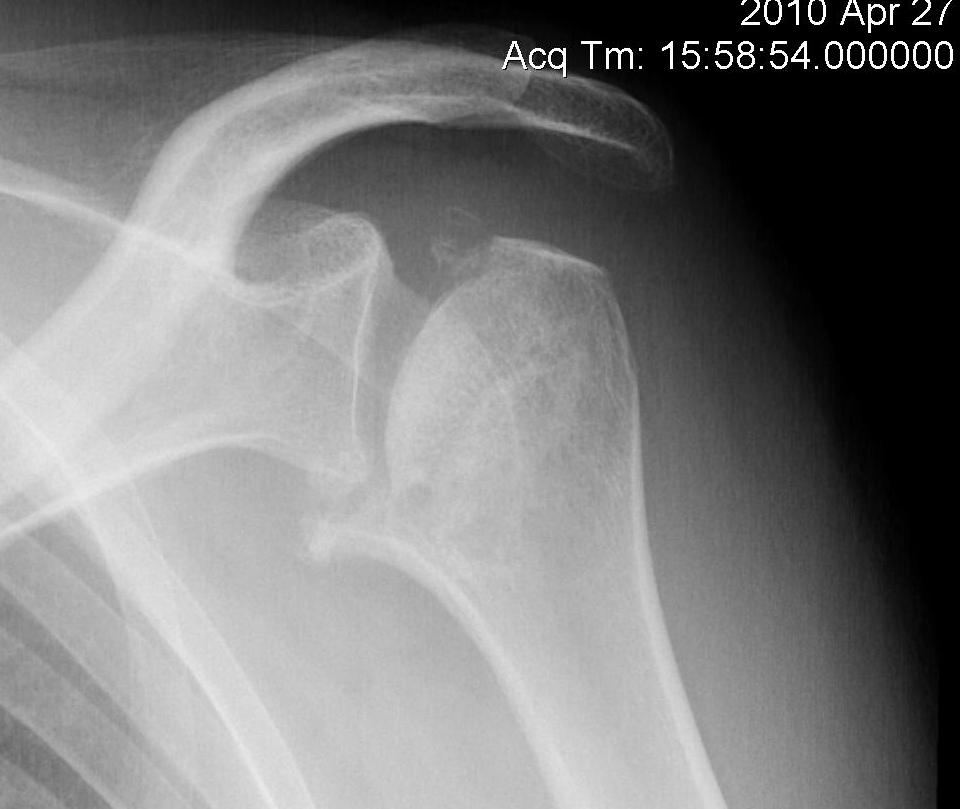

Classification / Cruess modification of Ficat-Arlet

Stage I - pre-xray change / diagnosed on MRI

Stage II - sphericity maintained / sclerotic changes in superior central head / crescent sign

Stage III - mild flattening articular surface

Stage IV - significant humeral collapse with loss integrity joint surface

Stage V - degeneration extends to involve glenoid

Superior head collapse at 90° mark

- area of peak contact stress in abduction

- glenoid rarely affected